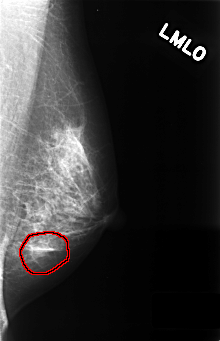

ics_version 1.0 filename C-0385-1 DATE_OF_STUDY 20 5 1996 PATIENT_AGE 40 FILM FILM_TYPE REGULAR DENSITY 2 DATE_DIGITIZED 9 11 1998 DIGITIZER LUMISYS LASER SEQUENCE LEFT_CC LINES 4464 PIXELS_PER_LINE 2872 BITS_PER_PIXEL 12 RESOLUTION 50 OVERLAY LEFT_MLO LINES 4432 PIXELS_PER_LINE 2856 BITS_PER_PIXEL 12 RESOLUTION 50 OVERLAY RIGHT_CC LINES 4560 PIXELS_PER_LINE 2776 BITS_PER_PIXEL 12 RESOLUTION 50 NON_OVERLAY RIGHT_MLO LINES 4576 PIXELS_PER_LINE 2808 BITS_PER_PIXEL 12 RESOLUTION 50 NON_OVERLAY |

FILE: C_0385_1.LEFT_MLO.OVERLAY TOTAL_ABNORMALITIES 1 ABNORMALITY 1 LESION_TYPE MASS SHAPE OVAL MARGINS ILL_DEFINED ASSESSMENT 4 SUBTLETY 4 PATHOLOGY BENIGN TOTAL_OUTLINES 1 BOUNDARY |